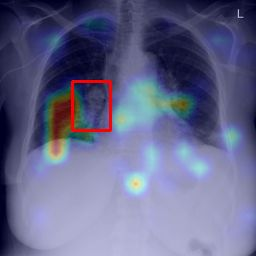

Deployments of artificial intelligence in medical diagnostics mandate not just accuracy and efficacy but also trust, emphasizing the need for explainability in machine decisions. The recent trend in automated medical image diagnostics leans towards the deployment of Transformer-based architectures, credited to their impressive capabilities. Since the self-attention feature of transformers contributes towards identifying crucial regions during the classification process, they enhance the trustability of the methods. However, the complex intricacies of these attention mechanisms may fall short of effectively pinpointing the regions of interest directly influencing AI decisions. Our research endeavors to innovate a unique attention block that underscores the correlation between 'regions' rather than 'pixels'. To address this challenge, we introduce an innovative system grounded in prototype learning, featuring an advanced self-attention mechanism that goes beyond conventional ad-hoc visual explanation techniques by offering comprehensible visual insights. A combined quantitative and qualitative methodological approach was used to demonstrate the effectiveness of the proposed method on the large-scale NIH chest X-ray dataset. Experimental results showed that our proposed method offers a promising direction for explainability, which can lead to the development of more trustable systems, which can facilitate easier and rapid adoption of such technology into routine clinics. The code is available at www.github.com/NUBagcilab/r2r_proto.